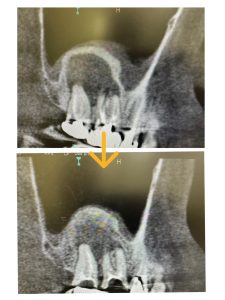

病巣改善❗️

スタッフM先生友人の根管治療開始5ヶ月後

昨年12月に題目「巨大病巣」で掲載済み

非常に良く治ってきている!

画像みれば分かるが、骨化が著しい、次回MTA根充